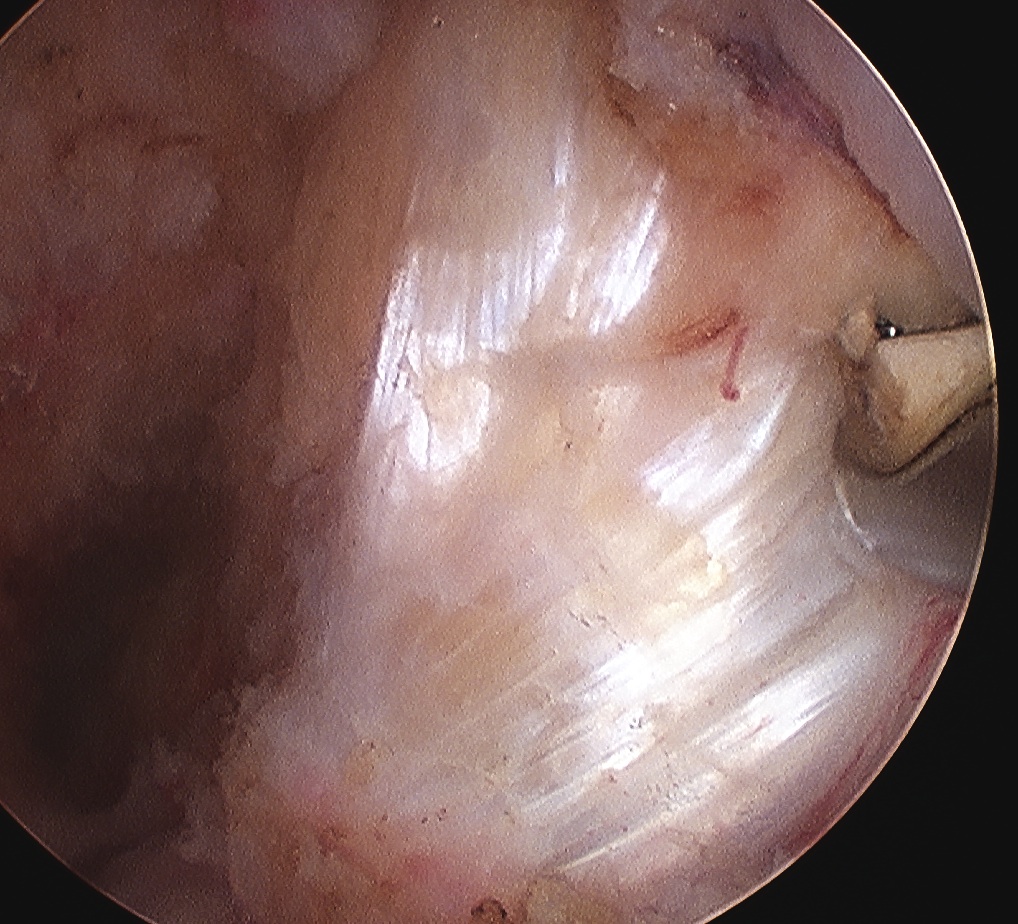

Arthroscopy

May miss tear as is extra-synovial

Chronic PCL tear from femur

Acute PCL femoral avulsion

Apparent ACL laxity due to PCL tear and posterior tibial sag; ACL tension restored with anterior drawer